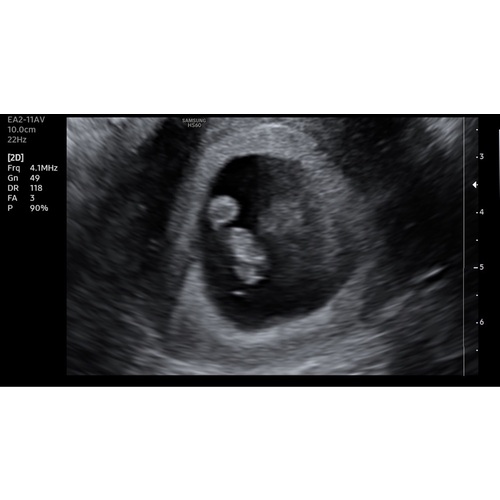

Vandaag de eerste echo gehad! Iets minder ver dan gedacht, 7+1 en een mooi kloppend hartje🥰 wie durft een gok te doen?😜💙💗 dit is een inwendige echo!

Vandaag de eerste echo gehad! Iets minder ver dan gedacht, 7+1 en een mooi ...